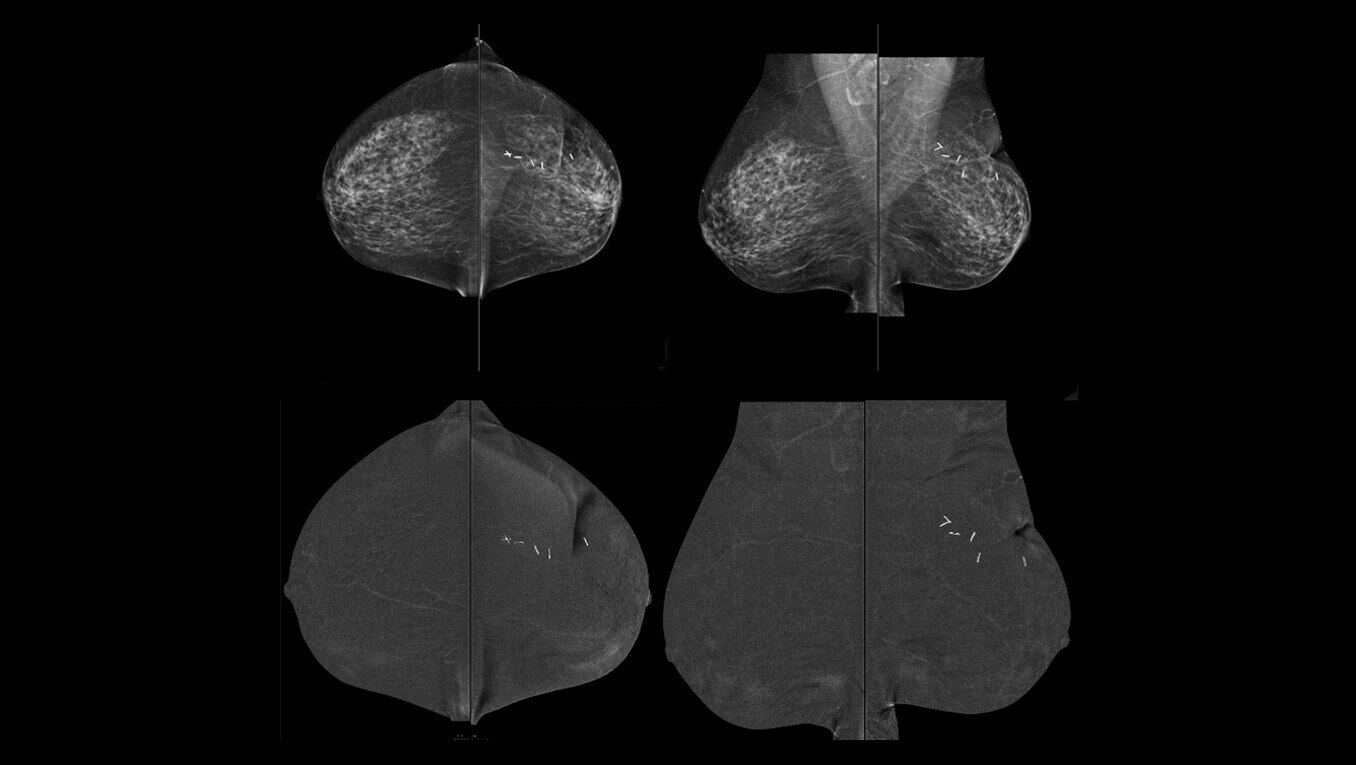

SenoBright™ HD

Contrast-Enhanced Mammography advanced application

Reduces the masking effect of breast tissue to reveal what matters1.